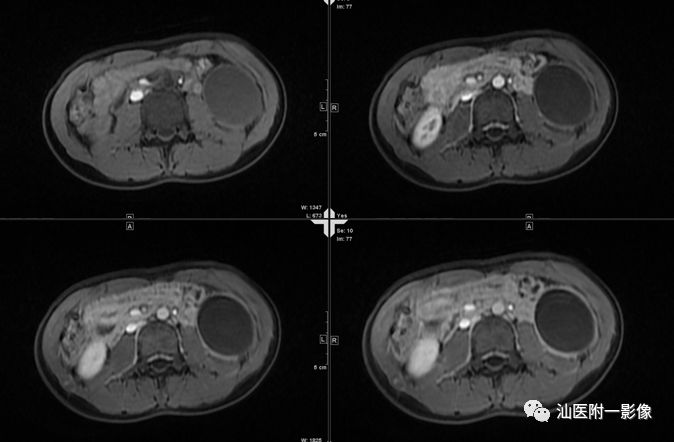

·男,15岁,上腹痛3天,加重半天

·3天前无明显诱因出现上腹痛,呈持续性痛。半天前症状突然加重。查体:全腹部腹肌紧张,左上腹部压痛及反跳痛明显。

·外院B超:左上腹囊性包块,考虑胰腺假性囊肿,未排其它

病例二 胰腺假性囊肿